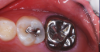

The occlusal-distolingual tooth preparation was completed, and a stainless steel orthodontic band was pressed into place to serve as a matrix (Figure 7). After two 60-second applications of a 5% glutaraldehyde/HEMA desensitizing solution, a self-etching bonding agent was painted on the enamel surfaces. An RMGI bioactive ionic resin-based composite was then injected in two portions (Figure 8), with 10-second light beam exposure between the injections. After the material was injected to overfill, the light beam was applied once more, for 20 seconds (Figure 9). The restoration was then trimmed and finished in the usual manner using large, round diamond burs at slow speed and diamond finishing burs on the axial surfaces (Figure 10). The self-etching bonding agent was then applied as a final glaze, and occlusal contacts were adjusted using articulating paper as a guide.

An RMGI bioactive ionic resin-based composite was injected after a self-etching bonding agent was applied.

Figure 8

Light exposure was applied for 20 seconds.

Figure 9

Immediate postoperative image

Figure 10